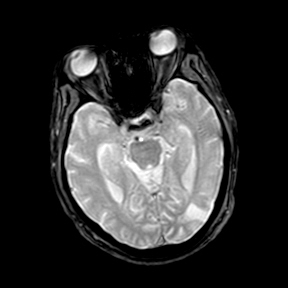

A 55 years old man with....